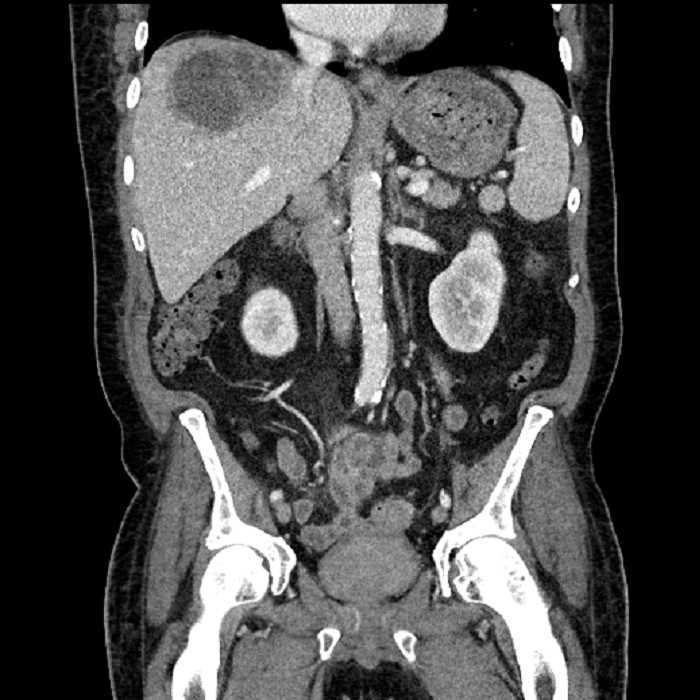

• Large fluid density structure in hepatic segments 7 and 8 measuring 10 x 7 x 7 cm with internal septation and circumferential ill-defined low density compatible with edema

• Peripherally enhancing subcapsular collections along the anterior margin of the left hepatic lobe measuring 3 x 1 cm and 2 x 1 cm

• Clearly marginated fluid density structure in segment 7 and several other scattered tiny hypodensities, which likely represent cysts

• High grade stenosis of the left common iliac artery, with the left internal and external iliac arteries remaining patent

• Incidental splenule

• Hepatic abscess

Acute sigmoid diverticulitis complicated by a small contained perforation and a large abscess in the right hepatic lobe. Additional small subcapsular abscesses along the anterior margin of the left hepatic lobe.

Additionally, loss of the normal fat plane between the peridiverticular collection and adjacent thickened loops of small bowel raises the potential for an enterocolonic fistula.

High grade stenosis of the left common iliac artery. The left external and internal iliac arteries are patent.

• The classic CT imaging appearance is a double target sign with internal low density surrounded by an internal enhancing rim (capsule) and a low density external rim (edema)

Hepatic abscess showing the double target sign with low density internally surrounded by a thin inner enhancing rim (red arrow) and ill-defined outer low density rim (yellow arrow). Blue arrow indicates an internal septation. Red arrows: additional smaller subcapsular abscesses. Red arrow: focal contained perforation associated with diverticulitis.